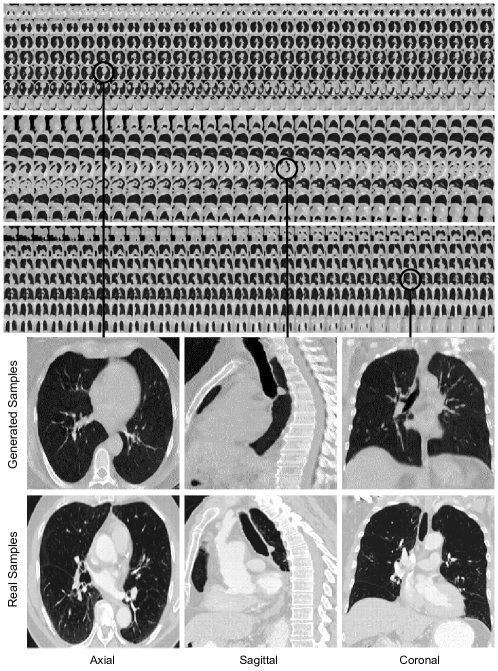

The evaluation of the generated CT-scans was designed to be done under two scrutinies: (1) qualitative inspection of the generated volumes from CT-SGAN where the diverse variation and consistency across all three views of axial, coronal, and sagittal were met (2) quantitative demonstration that synthetic data from CT-SGAN are valuable to build deep learning models for which limited training data are available. We evaluate the efficacy of data augmentation by three nodule detection classifier experiments (i) training with only real dataset (ii) training with only 10,000 synthetic volumes (iii) training with 10,000 synthetic volumes as a pretraining step and then continue to train on the real dataset (i.e., fine-tuning).

The visual qualitative evaluation of the generated volumes was studied based on three criteria: (1) Anatomical consistency of the generated slices, (2) Fidelity of generated slices to the real ones, and (3) diverse generation of CT-scans. Regarding the first two, Figure 1 shows these requirements were met as in thousand of generated CT-scans we rarely noticed any anomalies. For the high quality of the slices and slabs, we observed consideration of 3D slices and the inclusion of both patient- and slice-specific noises played important roles. As to the diversity in the generated CT-scans, i.e. to avoid mode collapse, and also to ensure stability in training, the discriminators’ losses contained the gradient penalty discussed in [15] introducing variations in the generated volumes. While CT-SGAN was preferably trained with Wasserstein loss [1], we did not notice a drastic change when the vanilla Jensen-Shannon loss was employed. Also, even though artifacts could appear in the generated CT-scans, the presence of them was partially related to the noise in real CT-scans produced by scanners.